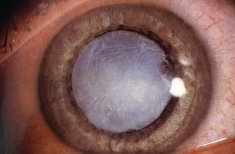

原發性青光眼泛指並非由其他疾病所致的青光眼。而繼發性青光眼是由其他眼疾或身體疾病引致,例如過熟的白內障、葡萄膜炎、眼球腫瘤、糖尿眼、或長期使用類固醇眼藥水。要治療繼發性青光眼,必須先處理引致青光眼的疾病。 -